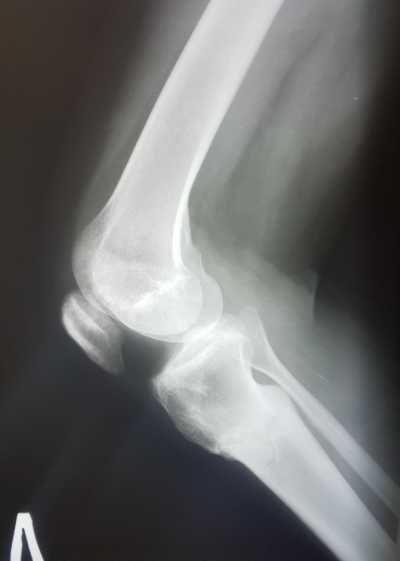

Рентген снимки через 1,5 месяца с момента снятия аппаратов